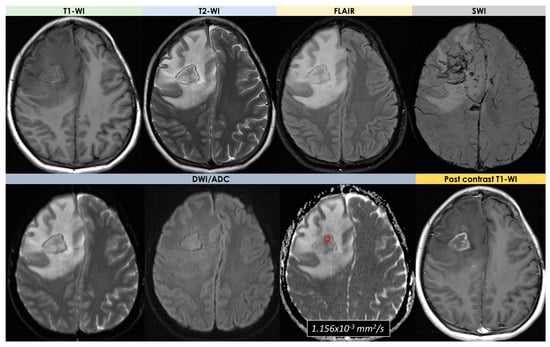

- Signal features: T1-Weighted Imaging (T1-WI) hypointense signal and intermediate to hyperintense signal on T2WI without diffusion restriction; intralesional microhemorrhages (small linear or punctate patterns on either Gradient Recalled Echo (GRE-T2*) or Susceptibility Weighted Imaging (SWI)) in 8/10 (80%) patients;

- Perilesional vasogenic edema (T2-WI high signal): marked in 5/10 (50%) patients and moderate in 5/5 10 (50%) patients;

- Enhancement patterns (parenchyma): all patients (10/10, 100%) had enhancing lesions with patchy parenchymal pattern in 5/10 (50%), “mottled appearance” (multiple small hypoenhancing areas within the patchy enhancing masses) in 3/10, small nodular pattern in 5/10, ring enhancement in 2/10, and linear (perivascular) enhancement pattern in 1/10 patients;

- Lesion number: two out of four patients had a single mass lesion and two out of four had multiple lesions (two hemorrhagic lesions in one case and multiple digitate-shaped enhancing lesions with edema in the second case);

- Lesion location: single lesions were in the suprasellar region and in the left frontal lobe white matter; multiple lesions were in the right frontal lobe in one case and in the right frontal white matter, corpus callosum, and external capsule in the second case;

- Signal features: the single lesions were an enhancing mass with edema in the suprasellar area with decreased signal on apparent diffusion coefficient (ADC) map, and a focal edematous mass-like lesion (2.1 cm) with T2-high T1-low signal lesion, gyral swelling, and increased ADC, respectively;

- Enhancement patterns: they were described as variable without further details;